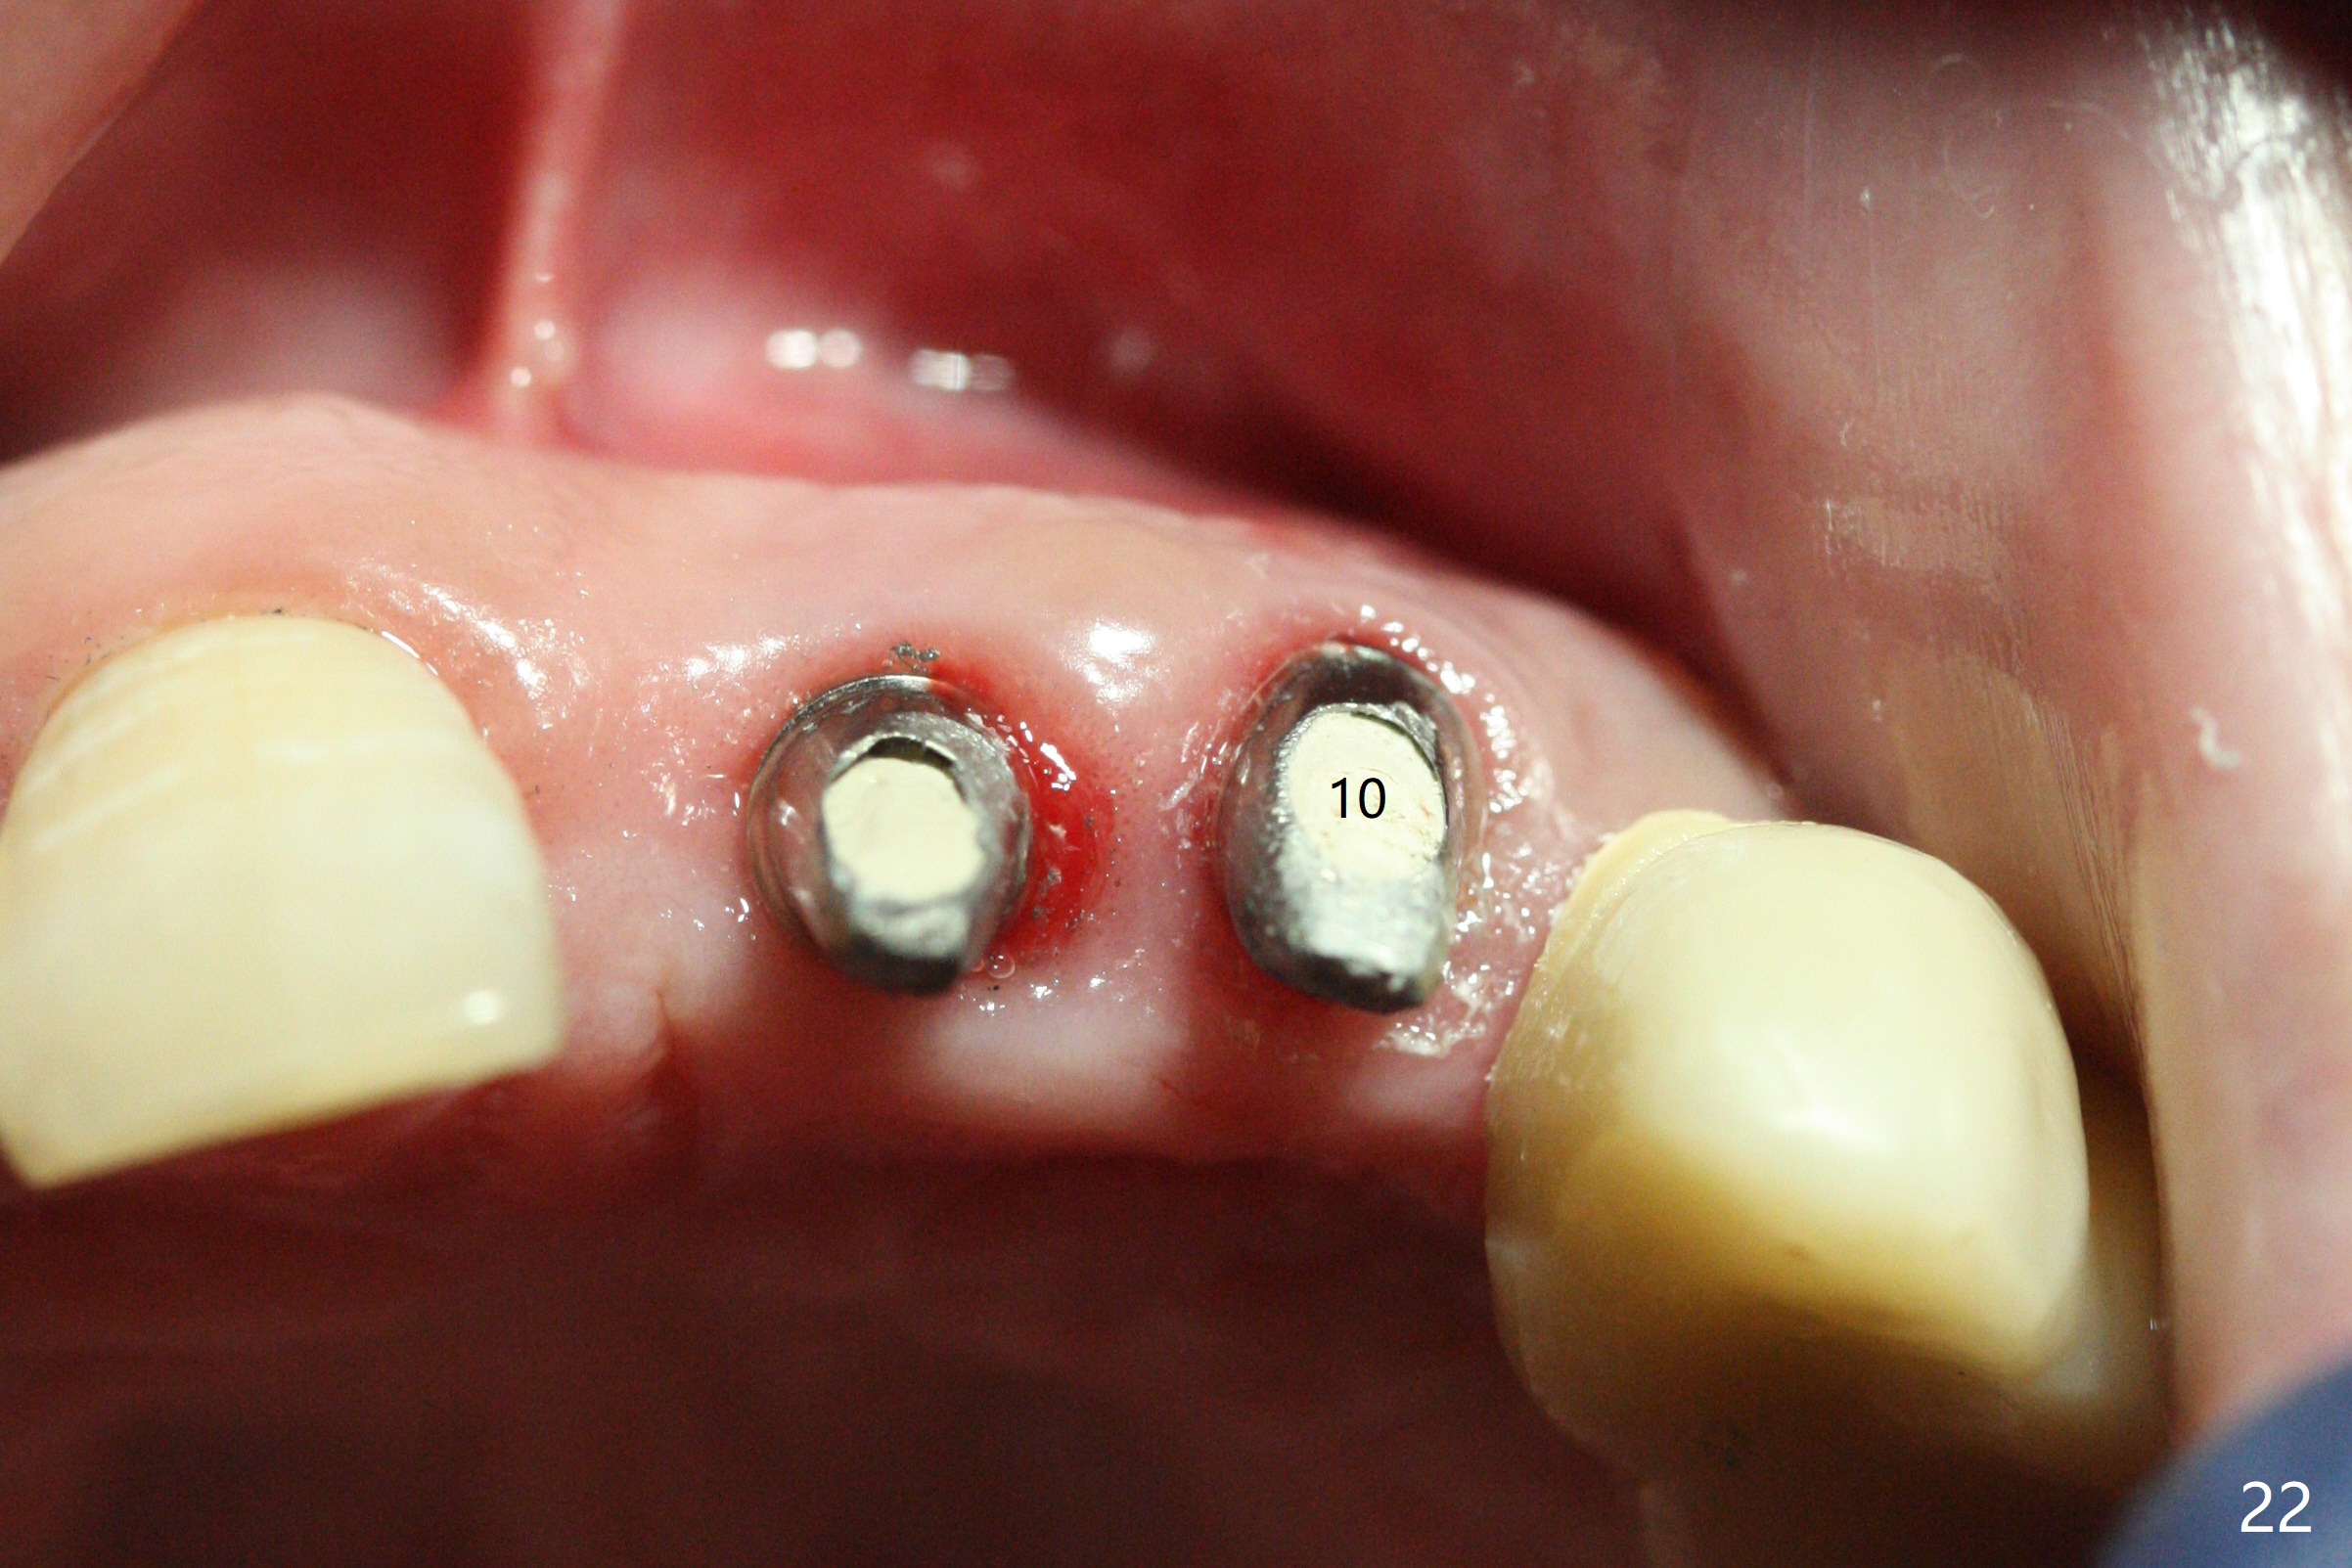

The dentition is poor except #6 and 8 (Fig.1). The gingiva is erythematous at #9-11 (Fig.2). The teeth #9 and 10 are extracted first; a 4x16 mm UF implant is placed at #9, while a 2 mm pilot drill is at the site of #10 (Fig.3). The implant at #9 is placed deeper with placement of 4.5x5.5(5) mm abutment; a 3.8x15 mm implant is placed at #10 initially (Fig.4). While the latter is placed deeper, a 4x16 mm implant is placed at #11 (Fig.5 after removal of #11-15 FPD (fixed partial denture)). In fact the trajectory at #11 is not difficult to be changed with 2 mm drill (Fig.6). After use of 3 mm drill, the implant is reinserted at #11 with ideal trajectory (Fig.7). After further seating of the implant at #11, graft is placed in the remaining sockets of #9-11 (Fig.8 *; later more graft is placed mesial to #11 implant (^)). Finally, a 4.5x7(5), 4.5x15° B (4) and 5.5x7(5) mm abutments are tightened and prepared (Fig.9) for splinted provisional at #9-10.